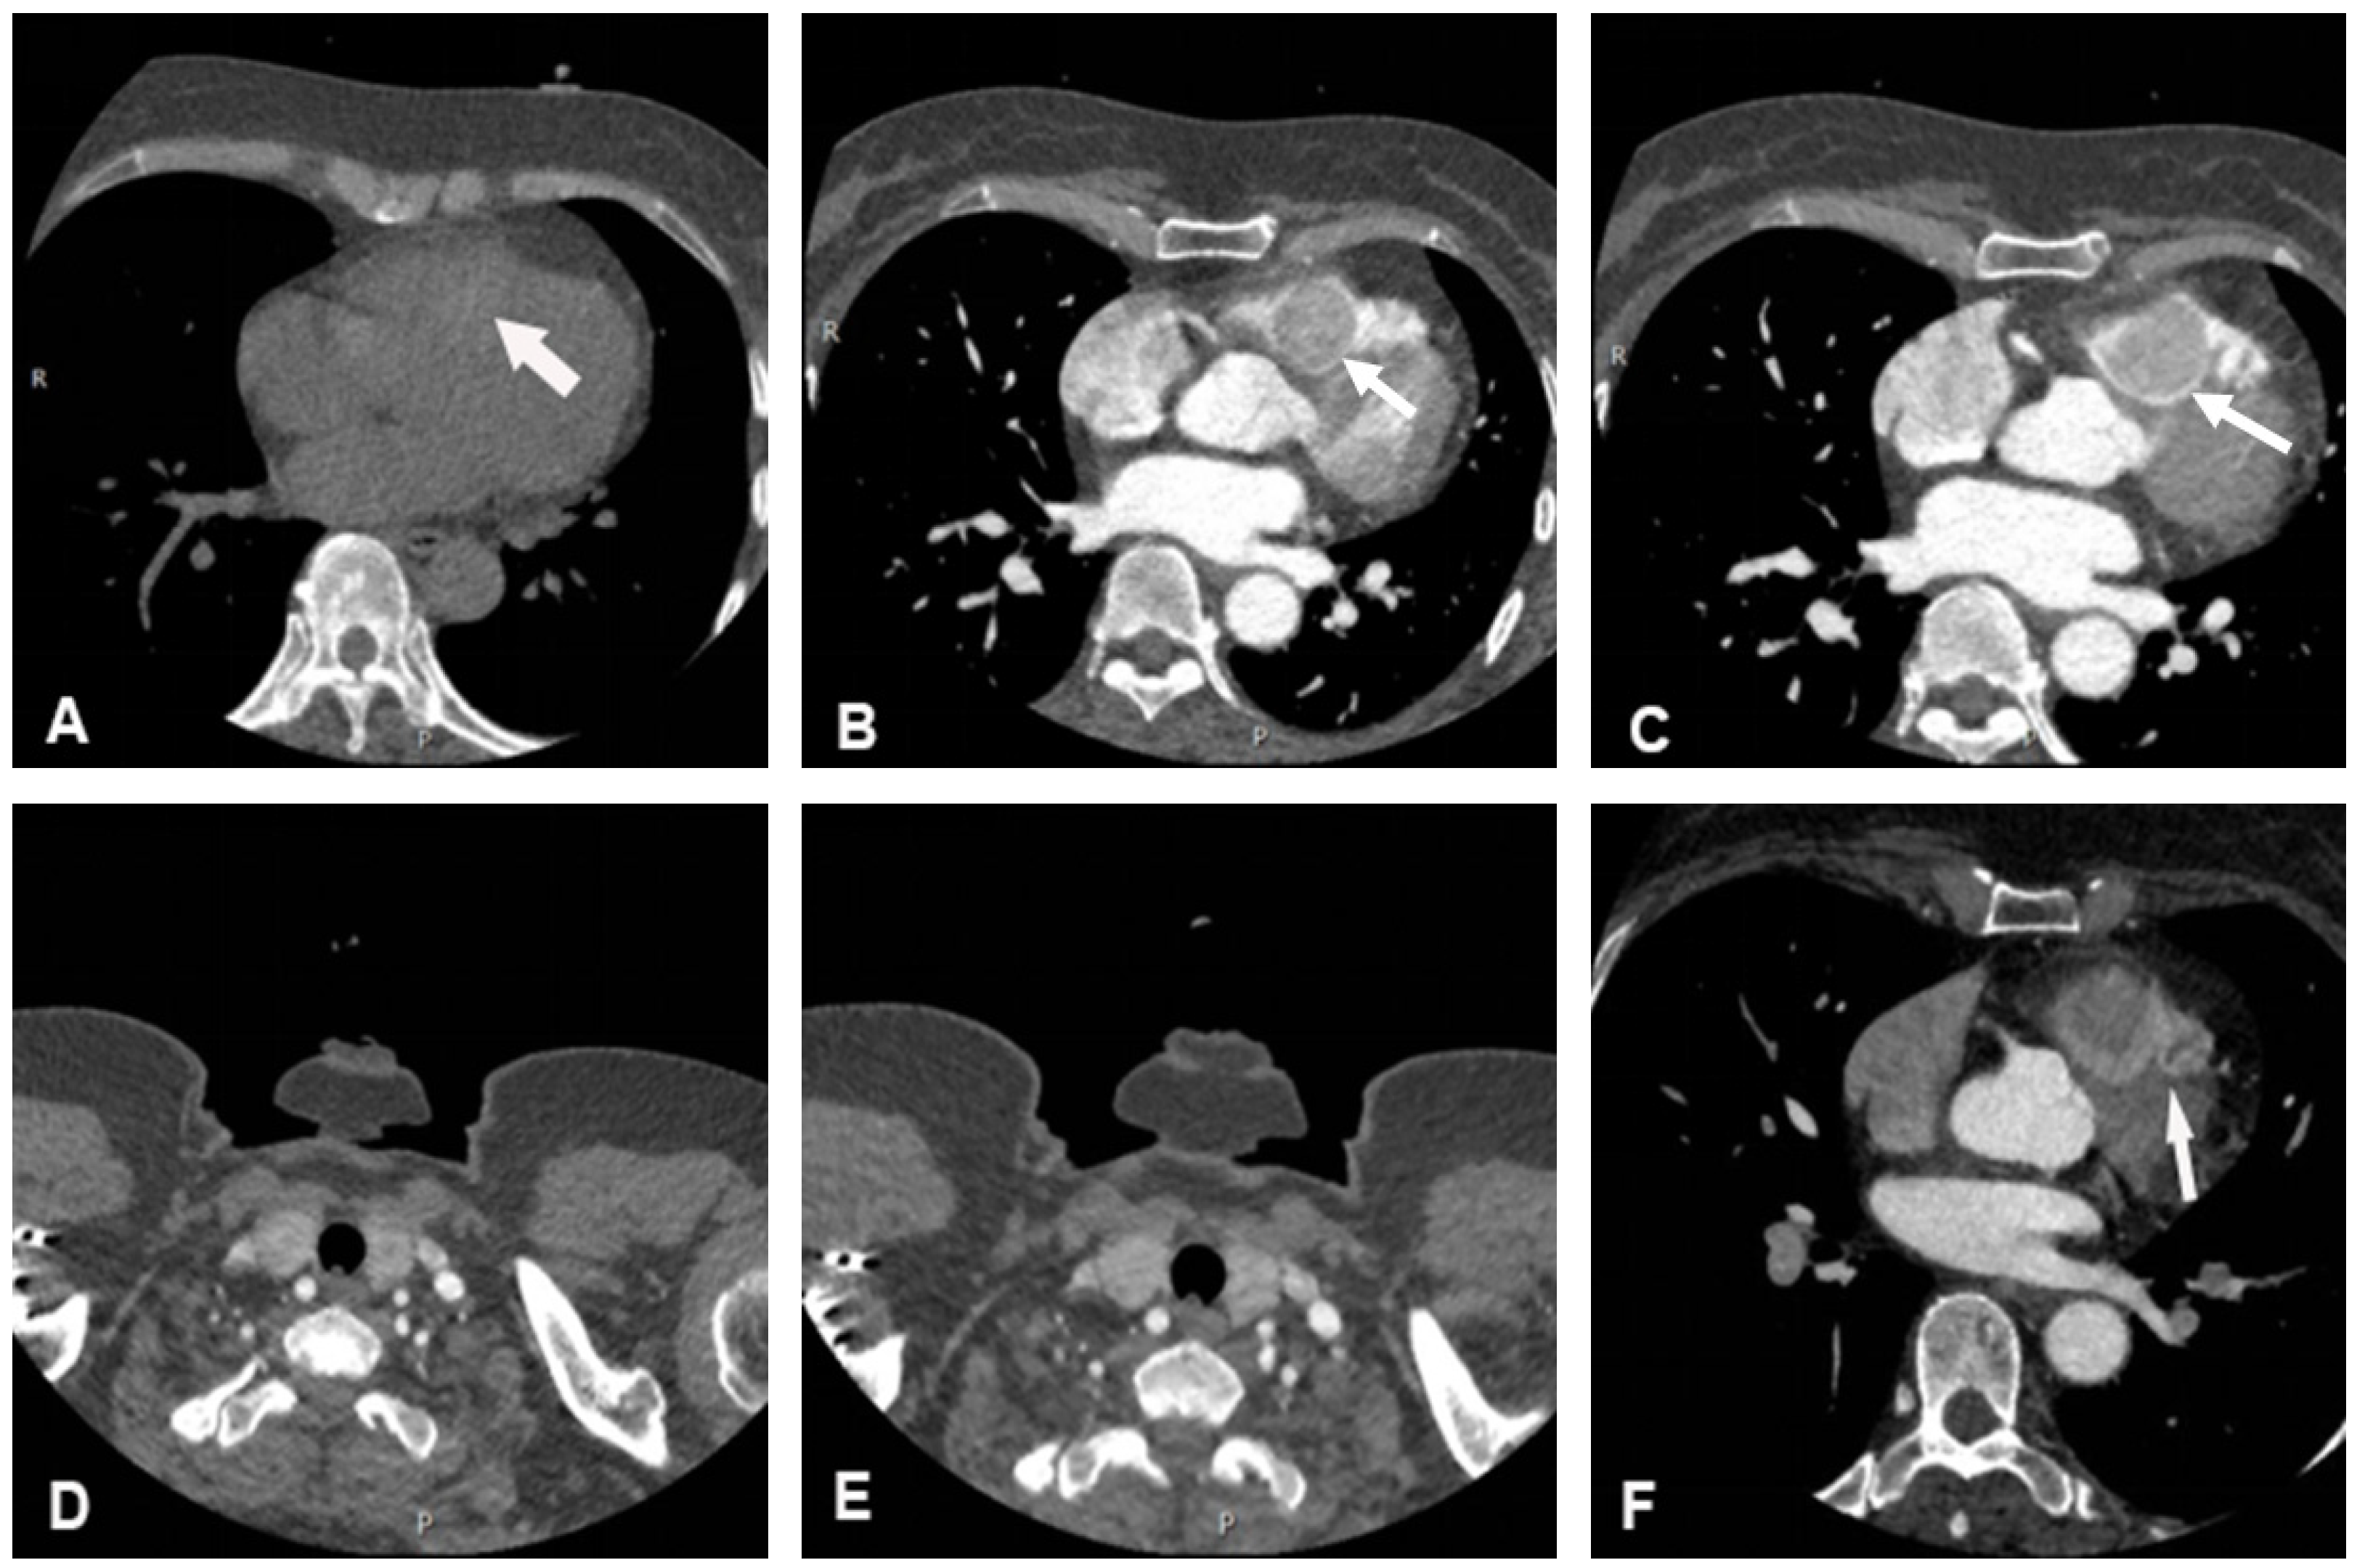

Cardiac non-contrast CT confirmed the presence of a round mass slightly high in density within the right ventricle, with a CT value of 70 Hounsfield Units (HU). In the contrast-enhanced scan, early, rapid, and homogeneous enhancement was noted, with a CT value of approximately 131 HU, and further enhancement with a CT value of approximately 213 HU, which was similar in density to the patient’s thyroid gland on non-contrast and contrast-enhanced CT (Figure 2). Coronary computed tomography angiography (CCTA) suggested that the mass was perfused by a branch arising from the left anterior descending artery (Figure 2).

Figure 2.

Cardiac CT imaging of the lesion. (A) The mass was slightly high in density on non-contrast CT scan. (B–E) The mass demonstrated obvious homogeneous enhancement on contrast-enhanced scan, which resembled the patient’s thyroid enhancement pattern. (F) CCTA images showed that the mass was perfused by a branch arising from the left anterior descending artery. White arrows indicate the location of the mass in each image.